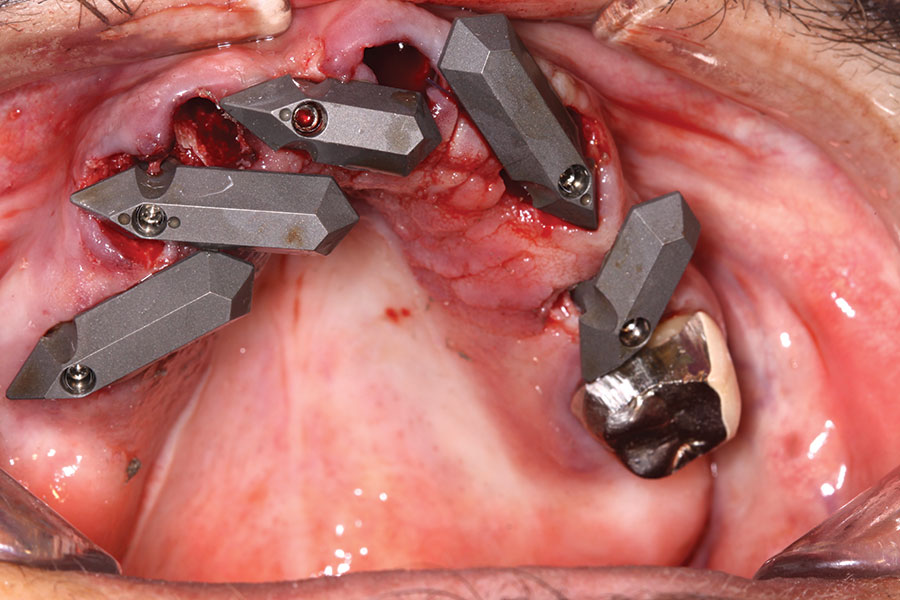

A week later the patient presented for surgery for extraction and replacement of her existing maxillary dentition with implants and a screw-retained provisional implant restoration. Teeth Nos. 2, 4, and 6 through 11, 13, and 14 were carefully extracted with attention paid to retaining site dimensions. Immediate implants were inserted into sites Nos. 4, 6, 8, 11, and 13 with high insertion torques in excess of

40 Ncm. Subsequently, multi-unit abutments were placed on all the implants and torqued to 30 Ncm, and scan gauges were placed on implant Nos. 8 and 11 (Figure 12 and Figure 13).

Fig 3. Initial extractions and scan gauges in place on multi-unit abutments secured to underlying implants.

Figure 3

Fig 4. Extractions completed; all implants, multi-unit abutments, and scan gauges in place.

Figure 4